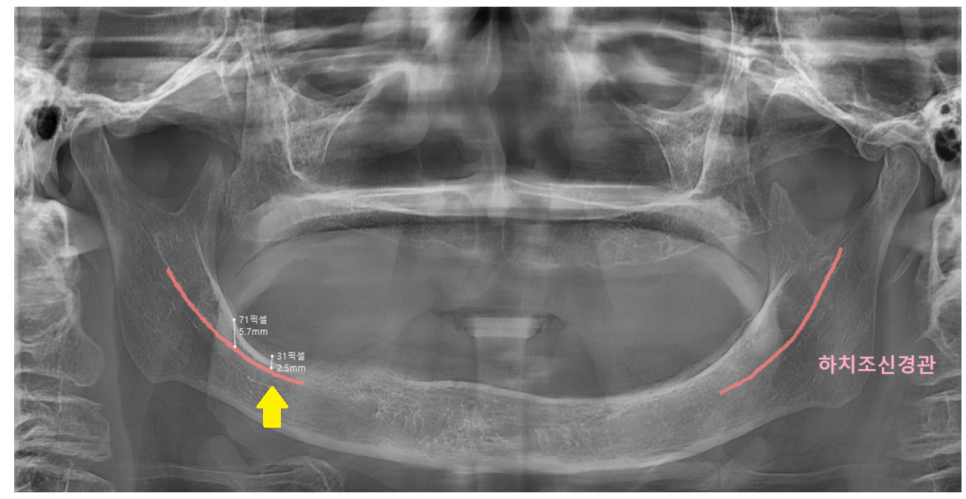

첫번째, 치조골 흡수가 심한 경우

틀니를 오래 낀 경우나

치아가 빠지고 시간이 오래 경과된 경우입니다.

임플란트를 어금니에 심기 위해서는

최소 8-10mm 길이가 필요합니다.

뼈 흡수가 심하게 되면

필요한 깊이만큼의 임플란트를 심지 못하게 되는데

이는 임플란트 수명에도 영향을 끼치게 됩니다.

짧은 임플란트는 씹는 힘을 온전히 견디기 어렵게 되거든요.